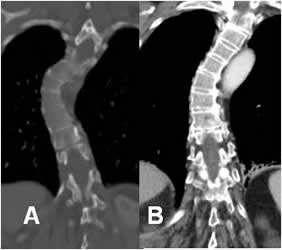

Fig 21. TAC.

A: TAC reconstrucción coronal en ventana de hueso y B: reconstrucción en ventana de tejido. Escoliosis dorsal derecha, sin encontrar signos de lesión estructural.

Fig 22. TAC 3D.

A: Rx AP y B: TAC reconstrucción 3D. Rotoescoliosis lumbar izquierda, con alteración en la densidad y configuración de los cuerpos inferiores.

C: TAC reconstrucción sagital en ventana de hueso y D: en ventana de tejido. Existe lesión lítica lumbar, que compromete varios cuerpos vertebrales y masa de tejidos blandos que invade el canal medular, por metástasis de tumor de mama.